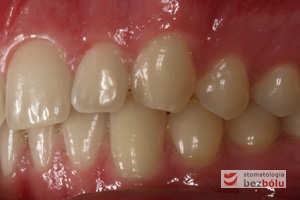

Młody 28-letni, pogodny, stale uśmiechnięty pacjent zgłosił się celem korekcji wad zębowych ograniczających pełną ekspresję uśmiechu. Głównym problemem był dodatkowy siekacz boczny (dwójka) po stronie prawej w łuku górnym. Dodatkowy ząb spowodował stłoczenia pozostałych zębów w łuku górnym oraz przesunięcie linii pośrodkowej. Obliczenia dostępnego miejsca dla siekacza bocznego wpłynęły na wybór zęba przeznaczonego do ekstrakcji. Usunięto dwójkę ustawioną dowargowo, zaś jej „siostrę bliźniaczkę” skierowaną w stronę podniebienia wprowadzono do łuku zębowego w drodze leczenia ortodontycznego. Problemem było szczelne zamknięcie szpary poekstrakcyjnej z powodu nadmiaru miejsca w kości. Wyrównano linię pośrodkową. Leczenie przeprowadzono jednym łukiem ortodontycznym górnym, dolny łuk zębowy nie wymagał założenia aparatu. Po zdjęciu zamków korekcję detali przeprowadzono z użyciem pozycjonera wykonanego w technice termoformingu. Stabilizację efektów leczenia zapewnił stały retainer klejony do powierzchni podniebiennych siekaczy górnych.